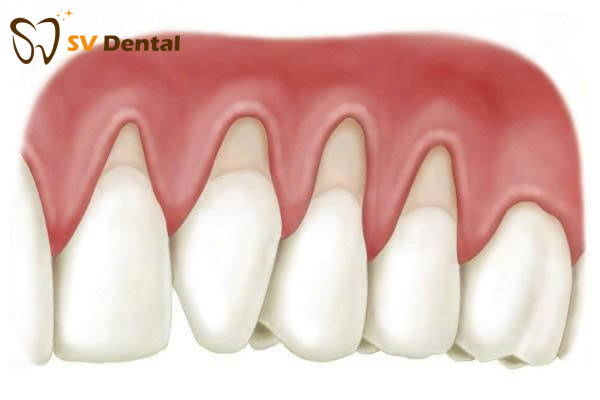

Tụt lợi là hiện tượng mô nướu rút xuống thấp, làm lộ phần chân răng và thậm chí cả ngà răng. Khi lợi tụt, răng không chỉ yếu đi mà còn gây đau, ê buốt và mất thẩm mỹ.